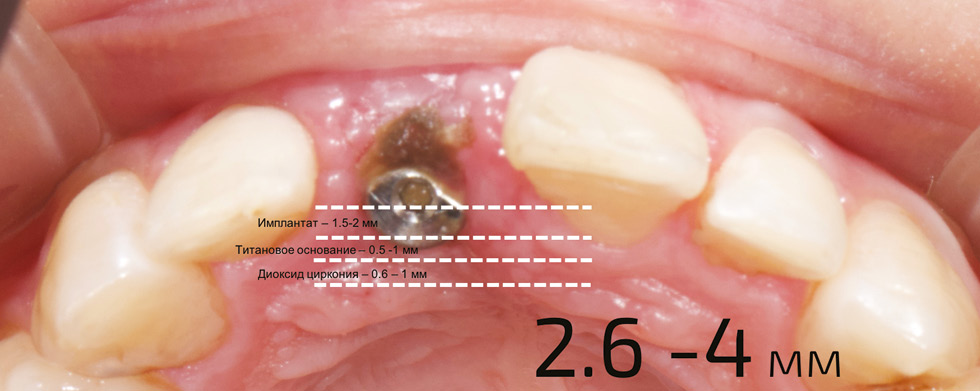

Каждому студенту было проведено компьютерное сканирование аппаратом 3 Shape (Дания). Далее в компьютерной программе ExoСAD (Италия) было проведено моделирование возможного увеличения объема коронки, фиксированной к имплантату, установленному в лунку удаленного зуба и смещенному к небной стенке, в среднем минимально равного 3 мм, из следующего расчета. Приблизительное смещение в небную сторону произошло на 1,5–2 мм, что составляет приблизительно половину диаметра имплантата со средним диаметром 4 мм, плюс титановое основание с толщиной стенки, в среднем равное 0,5–1 мм, плюс слой конструкционного материала на примере диоксида циркония, минимально равное 0,6–1 мм (рис. 6, 7).

Рис. 6. Увеличение размера коронки в небную сторону приблизительно на 3 мм

Fig. 6. Increased size of the crown palatially approximately 3 mm.